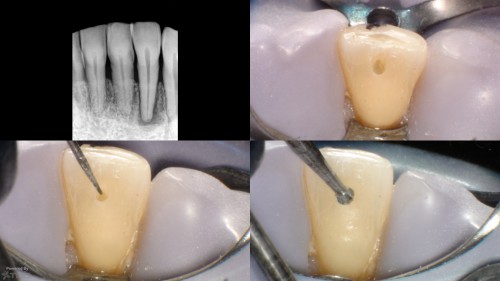

Death by ProTaper (R) and Round Bur averted.

By JK / August 14, 2018

In today for another tooth. Clinicals show the access with an SS White EG-4 and […]